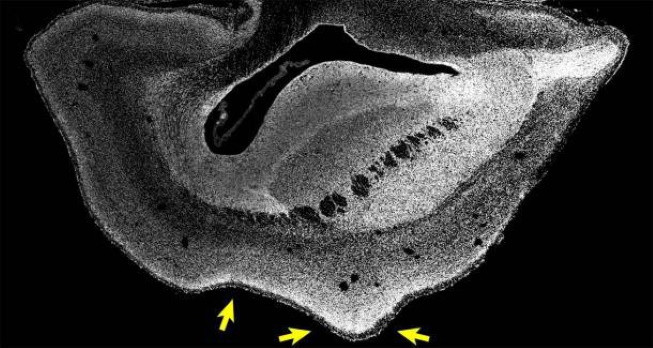

Изображение полушария мозга плода игрунки, выращенного с человеческим геном ARHGAP11B. Ядра клеток показаны белым цветом. Левая стрелка указывает на борозду (углубление или бороздку в коре головного мозга), а правая стрелка указывает на извилину (гребневидное возвышение).